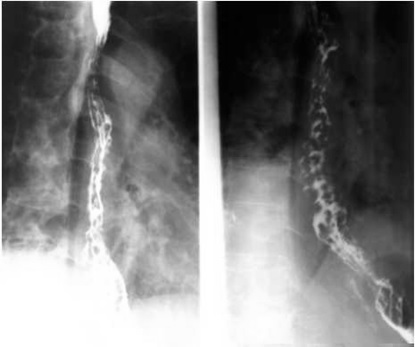

05卷-5.男性,胸骨后隐痛一年,请选择正确答案(本题满分2.00分)

本题答案:B

【该题针对“ 造影-食管静脉曲张 ”知识点进行考核】